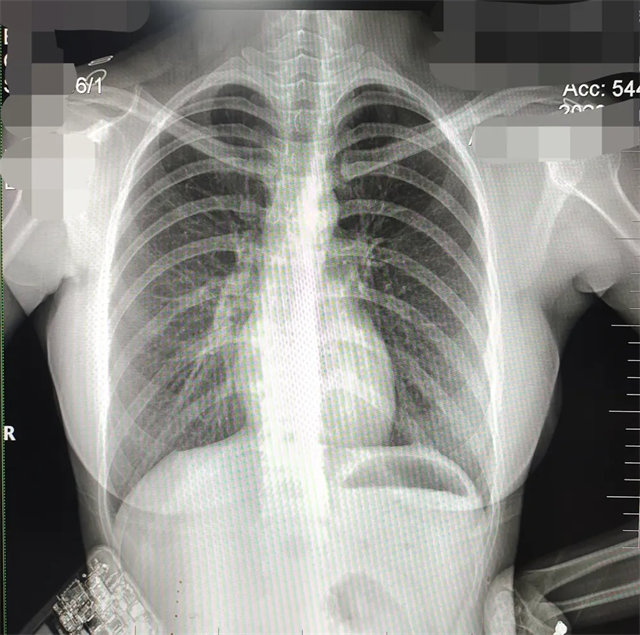

缺陷:肩胛骨未完全拉离肺野,吸气不完全,存在金属伪影遮挡,略有耸肩,且肺尖显示不好,图像颗粒感较强,管电流量不够,信噪比偏低。

解决:去除金属物品后,按标准体位,使患者双肩旋前与前胸一并紧贴成像件,适当调高mAs,然后深吸气后屏气曝光。